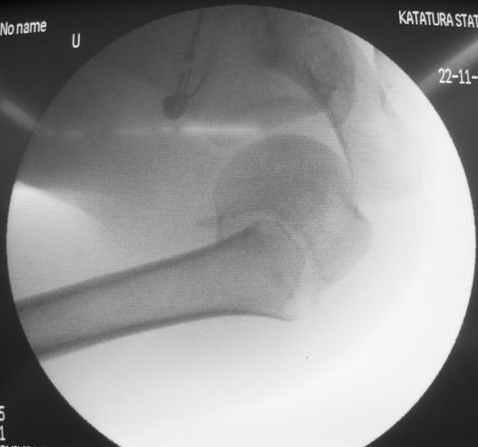

Сегодня взял больного повторно в операционную, не скажу, что повторная репозиция через неделю после первой попытки, была простая.

После удаления спиц попытался манипулировать отломками, но безуспешно, поэтому пришлось пользоваться периостальным элеватором, чтобы устранить смещение отломков и перепровести спицы. Проверил и перепроверил стабильность фиксации под ЭОПом, завтра Рг- будет готов, вот и поглядим....

Посылаю послеоперационные Рг граммы.

Всего Доброго,

Поздравляю, получилось просто замечательно. Если можно, расскажи чуть подробнее, как делали - как вправляли, как вводили спицы, поворачивали ли их?

Я и сам доволен результатом. В предпоследнем письме я кратко описал ход операции - закрыто репонировать не удалось( 2 недели с момента травмы и 1 неделя после неудачной репозиции) после удаления пучков спиц, пришлось сделать - 2см разрез на уровне перелома и с помощью периостального элеватора (золотое правило механики) *одеть* головку на дистальный отломок.

Спицы проводил через старые отверстия, вращая пучок импактором- направителем при его введении в головку.